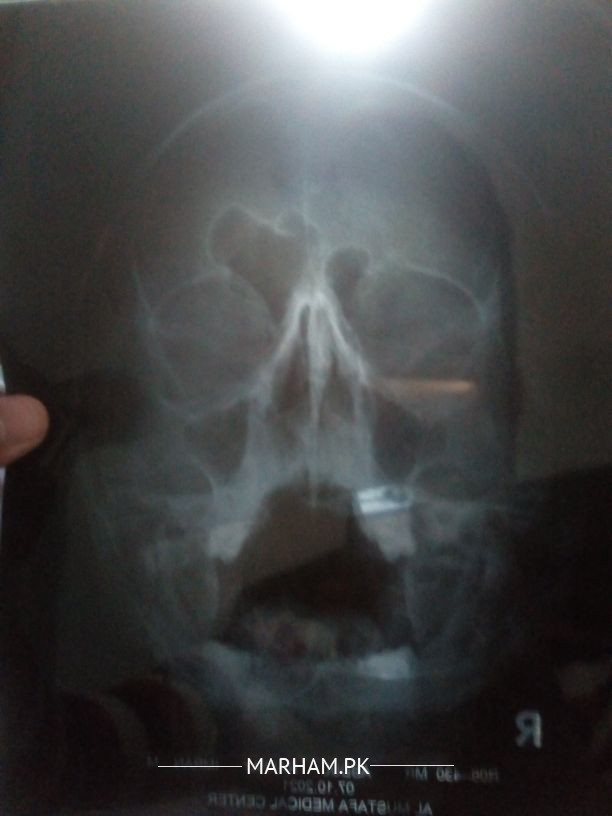

I can't breath properly from years due to my right nostril blocked, which is effecting normal airways. Which surgery is suitable for it pls suggest Ent surgeon. As one Dr said its not the case of septoplasty.

Proper examination is required for diagnosis and treatment X-ray shows Septal position is straight forward.